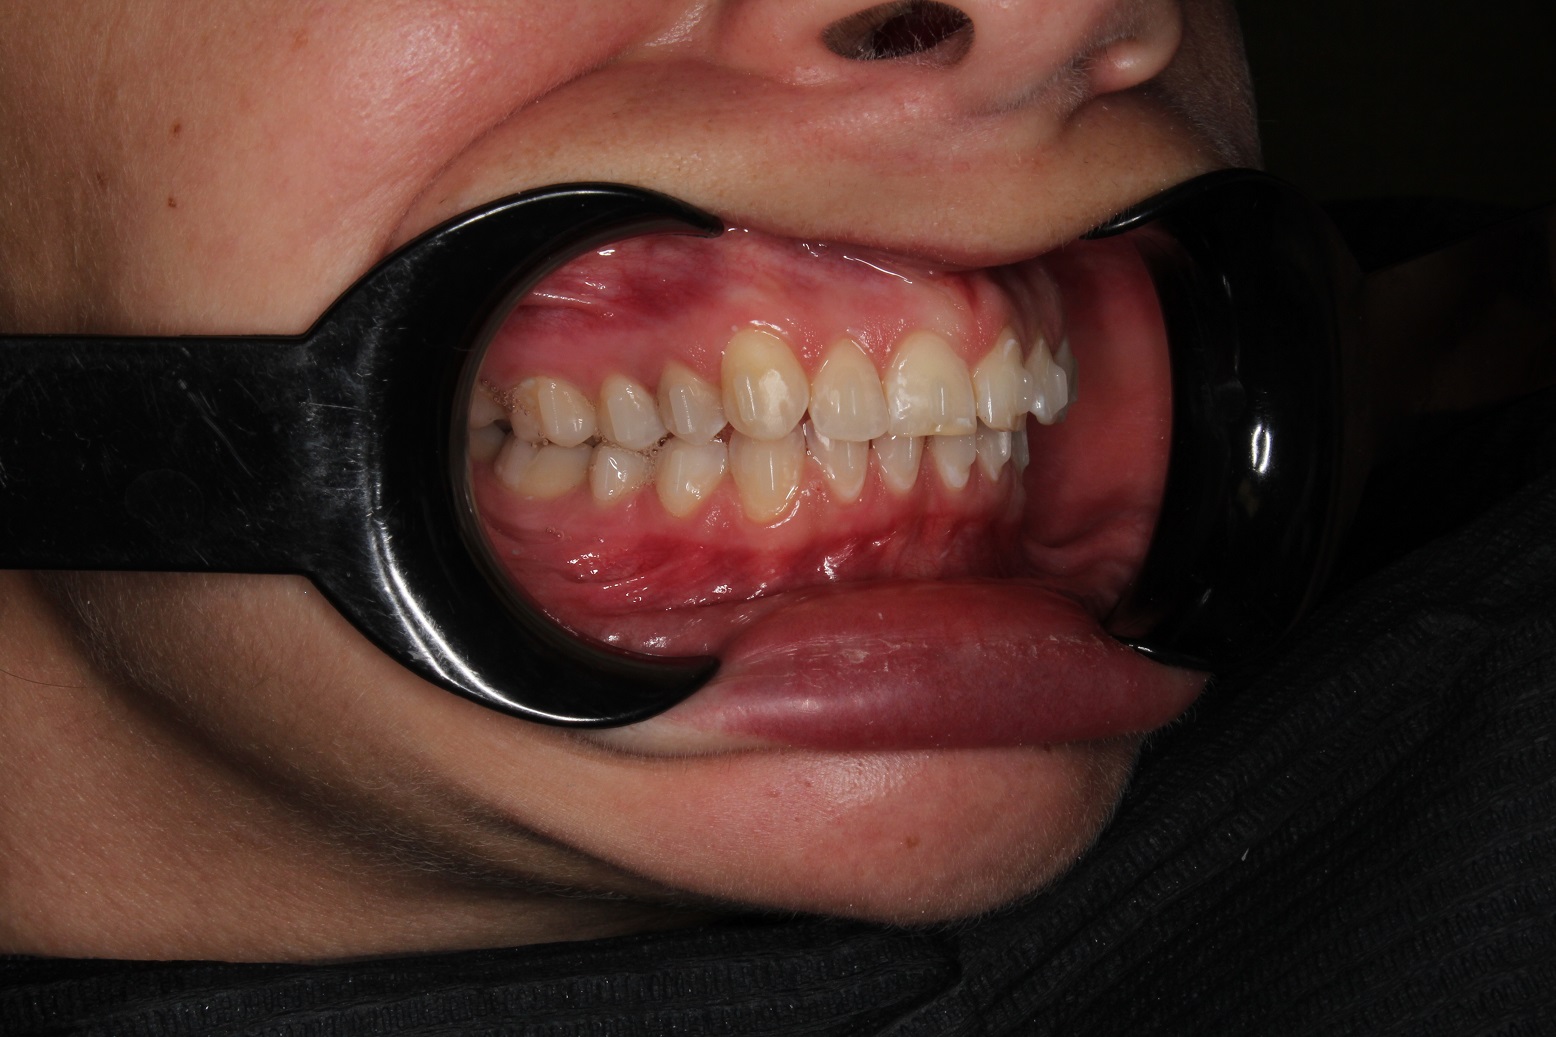

До и После: Лечение глубокого прикуса с помощью элайнеров Eurokappa